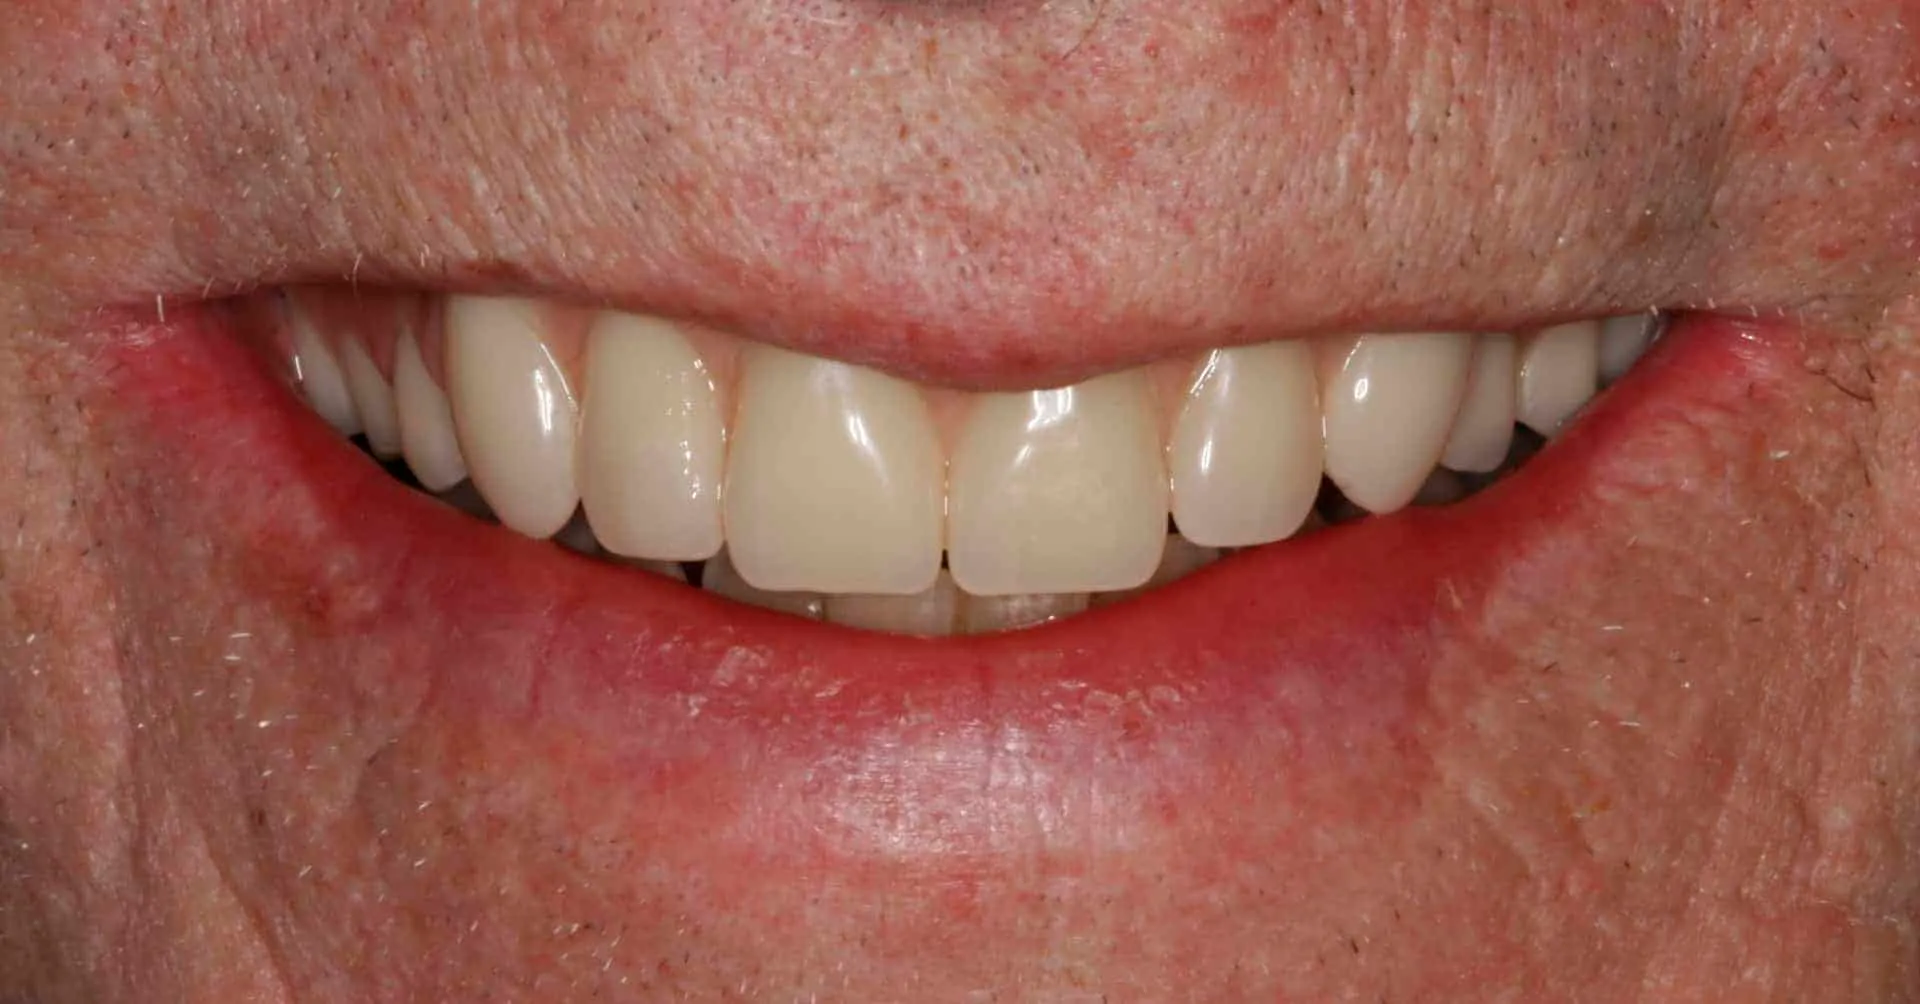

After: Maxillary (upper), acrylic fused to metal, fixed (hybrid) screw-retained (retrievable) restoration supported by 6 titanium root form dental implants. The restoration is fixed, therefore only Dr. Leopardi can remove it for routine maintenance and hygiene, as needed. The patient cleans the fixed restoration as he does his natural lower teeth, with a tooth-brush, floss and water-pick. The outcome is improved function, mastication/diet, aesthetics and quality of life.